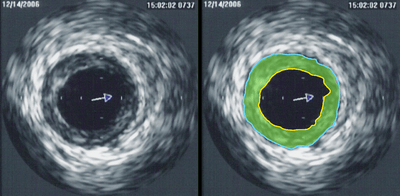

Intravascular ultrasound (IVUS) is a medical imaging methodology using a specially designed catheter with a miniaturized ultrasound probe attached to the distal end of the catheter. The proximal end of the catheter is attached to computerized ultrasound equipment. It allows the application of ultrasound technology, such as piezoelectric transducer or CMUT, to see from inside blood vessels out through the surrounding blood column, visualizing the endothelium (inner wall) of blood vessels in living individuals.[1]

The (a) blood vessel wall inner lining, (b) atheromatous disease within the wall and (c) connective tissues covering the outer surface of the blood vessel are echogenic, i.e. they return echoes making them visible on the ultrasound display.

By contrast, the blood itself and the healthy muscular tissue portion of the blood vessel wall is relatively echolucent, just black circular spaces, in the images.

Heavy calcium deposits in the blood vessel wall both heavily reflect sound, i.e. are very echogenic, but are also distinguishable by shadowing. Heavy calcification blocks sound transmission beyond and so, in the echo images, are seen as both very bright areas but with black shadows behind (from the vantage point of the catheter tip emitting the ultrasound waves).